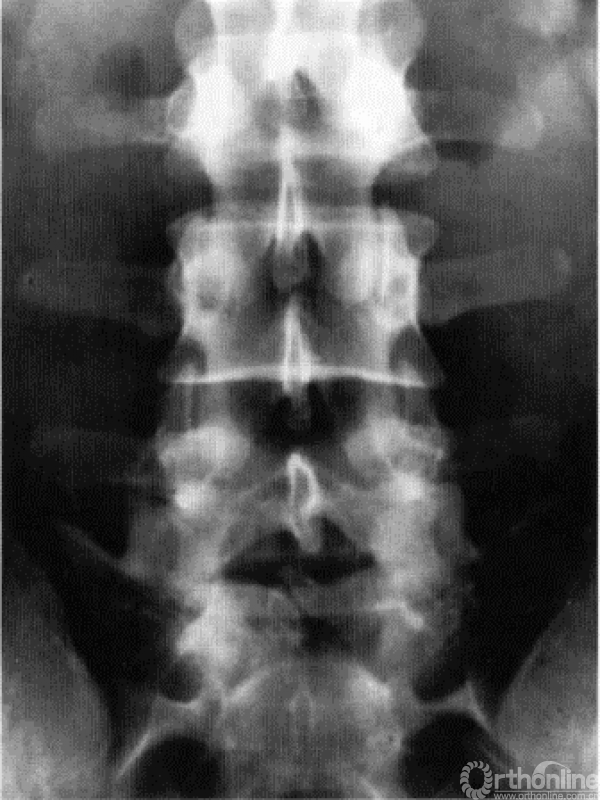

现在让我们重新探讨一下后方的结构(图18.11)(同时再回头看看图18.3)。在后方的6个解剖结构中,仅有2个只位于一个层面,即椎弓根及横突,他们仅位于第三层。

上关节突不仅位于第三层,同时还有一部分遮挡上一节段的椎间隙(第一层)。类似地,下关节突跨越第一和第二层;椎板的头侧缘可遮挡同一解剖节段的第三层,同样其尾侧缘可遮挡该解剖节段的第一层(图18.12)。

图18.11 后方的解剖结构就像加盖在房子上的屋顶(左图)。现在不要将房子侧卧,我们将其直立起来,这样看起来,就同我们在手术台上看到的后方解剖结构一样了

图18.12 正位X线片显示3层分区与后方解剖结构的重叠关系。注意L5椎板下缘(与椎间隙无重叠)与L3椎板下缘(其椎板的下缘重叠到L4的第3层)与前方3层分区重叠关系的变化